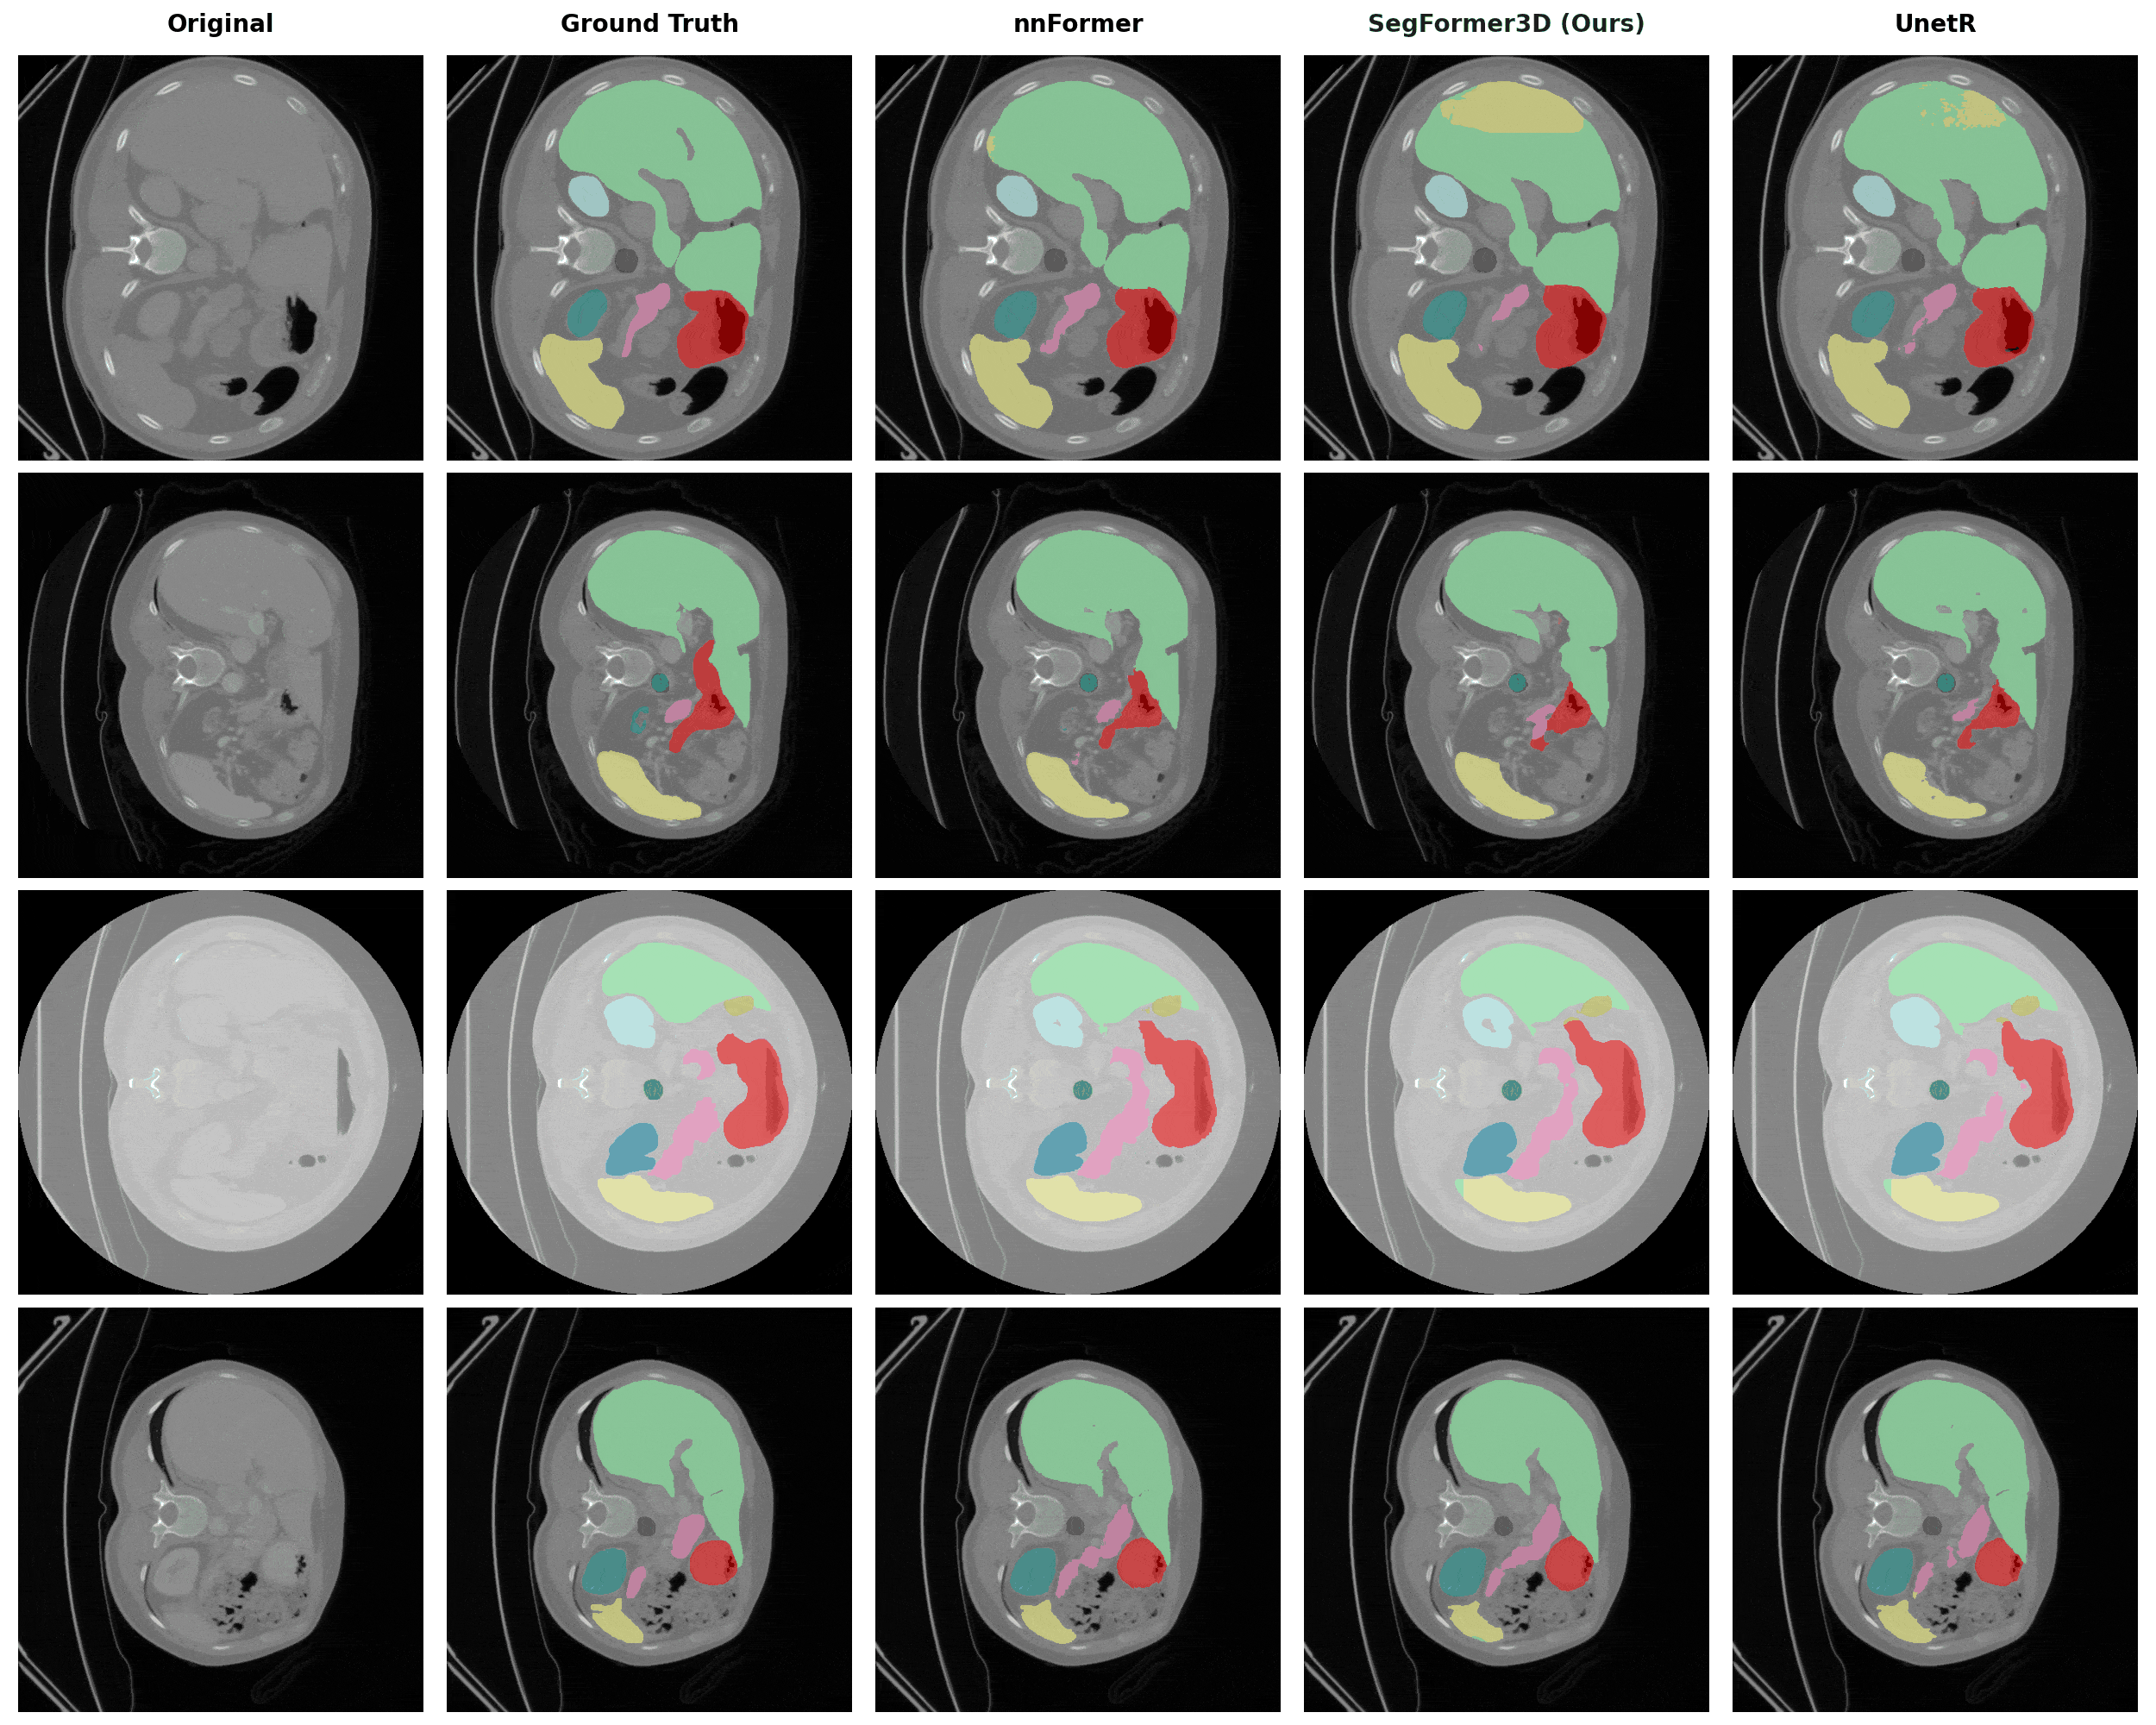

Qualitative Results

We compare SegFormer3D (highlighted in green) against state-of-the-art baselines on three medical imaging datasets. Despite being significantly lighter, our model produces highly accurate segmentation masks across all datasets.

Multi-Organ CT Segmentation (Synapse)

Segmentation of 8 abdominal organs including spleen, kidneys, liver, stomach, gallbladder, pancreas, and aorta.

Synapse Segmentation Results